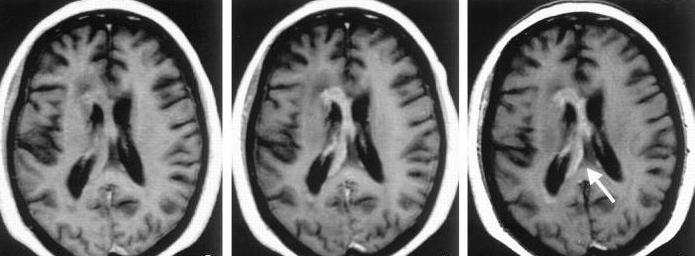

При анализе результатов исследования обращают внимание на М-эхо, а также на начальный и конечный комплексы. Патологические изменения выявляются при смещении средней линии более чем на 2 мм. Эхоэнцефалография головного мозга позволяет их обнаружить. Интерпретация результатов осуществляется специалистом с учетом следующих норм:

- М-эхо должно находиться в центре, то есть MD = MS. Расщепление сигнала, исходящего от него, указывает на внутричерепную гипертензию. Нормальные колебания пульсации М-эха составляют от 10 до 30 %. Увеличение этого показателя может свидетельствовать о гипертензионно-гидроцефальном синдроме.

- Среднеселлярный индекс в норме составляет 3,9-4,1.

- Смещение М-эха на 5 мм вверх указывает на геморрагический инсульт, а вниз – на ишемию.

- В норме должны быть соблюдены индексы III желудочка (22-24) и медиальной стенки (4-5).

Описание метода [ править | править код ]

Эхосигналы, возникающие при проведении эхоэнцефалоскопии, формируются на границах различных сред, таких как кости черепа, твердая мозговая оболочка, ликвор, ткань головного мозга и патологические образования. Центральный и стабильный сигнал с максимальной амплитудой, известный как М-эхо, создаётся срединными анатомическими структурами головного мозга, расположенными в сагиттальной плоскости (например, третий желудочек, эпифиз, большой серповидный отросток твердой мозговой оболочки и другие). Для оценки смещения срединных структур головного мозга измеряется расстояние между первым, начальным комплексом (импульсы от поверхностных структур головы) и сигналом с наибольшей амплитудой (М-эхо). В норме это расстояние при исследовании симметричных точек правой и левой сторон головы одинаково и составляет у взрослых 65—80 мм (в зависимости от размера головы). Однако при наличии объемного процесса в одном из полушарий головного мозга М-эхо смещается в противоположную сторону, что указывает на дислокацию срединных структур.